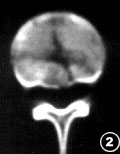

3. 脊柱:常规X线平片虽能显示脊柱骨折或骨脱位,但椎体裂隙性骨折及椎体后部骨折容易漏诊,有无骨折碎片突入椎管也显示不清。CT可清楚显示骨折细节,特别是椎体后部结构的骨折与移位的碎骨片,还能观察椎管形态和狭窄程度(图2),椎间盘突出与硬脊膜外血肿等均可一次扫描得出诊断。